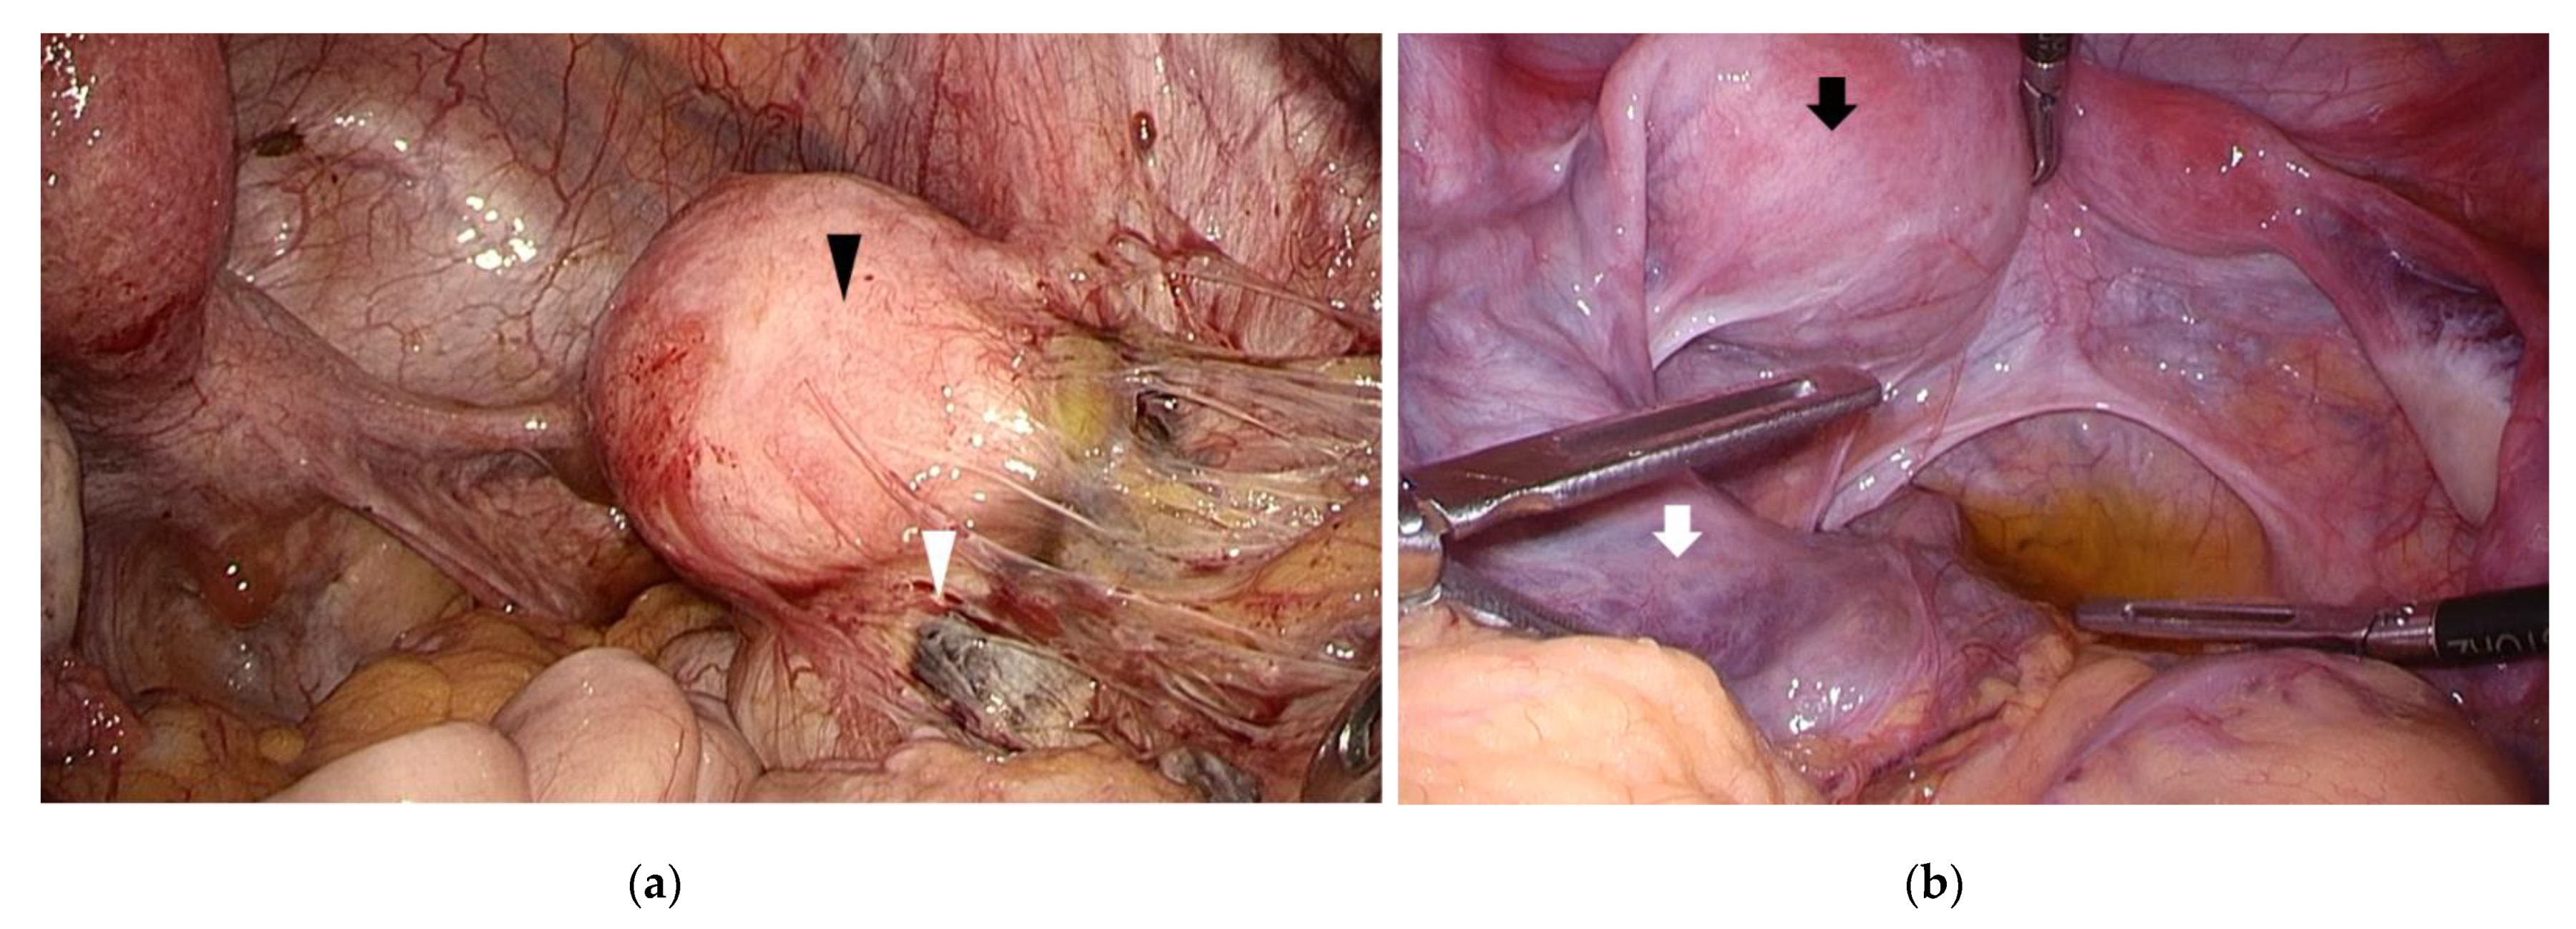

Congenital uterine malformations with outflow obstruction include obstructive Müllerian duct malformations such as unicornuate uterus with non-communicating functional horn, or double uterus with an obstructed vagina. Increased menstrual blood reflux, caused by outflow obstruction, may increase the susceptibility to endometriosis in women with obstructive malformations. In a study of 85 adolescent women younger than 19 years of age, none of the 44 women with genital malformations had a family history of endometriosis, while 8 (19.5%) of the 41 women without genital malformations had a positive family history [42]. In a study of 64 women with Müllerian duct anomalies accompanying functional endometrium and patent fallopian tube, 10 out of 13 (77%) women with outflow obstruction had endometriosis, while only 16 out of 43 women (37%) without outflow obstruction had endometriosis [43]. These results confirm outflow obstruction to be a risk factor for endometriosis, supporting the theory of retrograde menstruation and implantation (Figure 2). Obstructive malformations may also cause earlier onset of endometriosis among young women. Yang et al. examined 63 women younger than 21 years of age with a pathologically confirmed diagnosis of endometriosis. Although the mean age at diagnosis was 18.4 ± 1.8, women with obstructive malformations were diagnosed much younger than those without (16.21 versus 19.0 years). Among the 15 young women with obstructive malformations, the ovaries were involved in 14 women (93%), while the pouch of Douglas and the uterosacral ligaments were affected in only two women (13%). On the other hand, among the 48 women without obstructive malformations, the pouch of Douglas and the uterosacral ligaments were affected in 26 women (54%; p = 0.005) [44]. In adolescents with congenital outflow obstruction, endometriosis is treated by modifying the obstruction under laparoscopic surgery, rather than with medical therapy. Song et al. reported that the mean age at the time of surgery in adolescents with obstructive malformation is reported to be significantly less than those without obstructive malformation (15.1 ± 2.4 versus 17.6 ± 1.7 years; p < 0.001). The delay from symptom onset to surgery was also shorter (1.5 ± 1.3 versus 2.3 ± 2.1 years; p = 0.033) [42]. Surgery drastically alleviates pain, emphasizing the importance of evaluating obstructive malformations in younger adolescent women with pelvic pain. Furthermore, it has been reported that recurrence does not occur after surgical correction of outflow obstruction [10,45].

Figure 2.

Congenital uterine anomaly and outflow obstruction. (a) A left unicornuate uterus with non-communicating functional horn (black arrowhead) was observed. An endometriotic cyst (white arrowhead) was found in the right ovary with inflammatory adhesion surrounding the right adnexa; (b) A right unicornuate uterus presenting with hematometra accompanying a non-communicating functional horn (black arrow). Left hematosalpinx (white arrow) and left endometriotic cyst was observed.